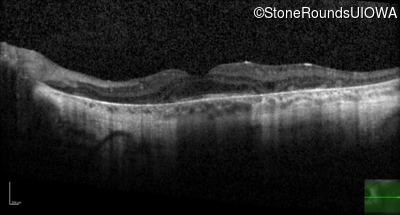

Optical Coherence Tomography - Right - 20/32 sc

Exemplar / OCT Stack

OCT Stack